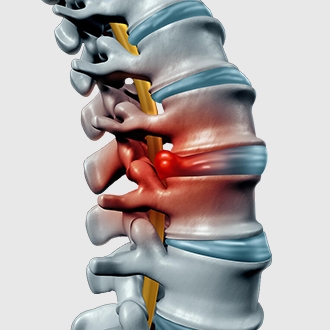

Thoát vị đĩa đệm

Thoát vị đĩa đệm là bệnh lý xảy ra khi nhân nhầy của đệm cột sống chệch ra khỏi vị trí bình thường, xuyên qua dây chằng và chèn ép vào cột sống hoặc các dây thần kinh, gây đau nhức tê bì cột sống. Hai vị trí thường